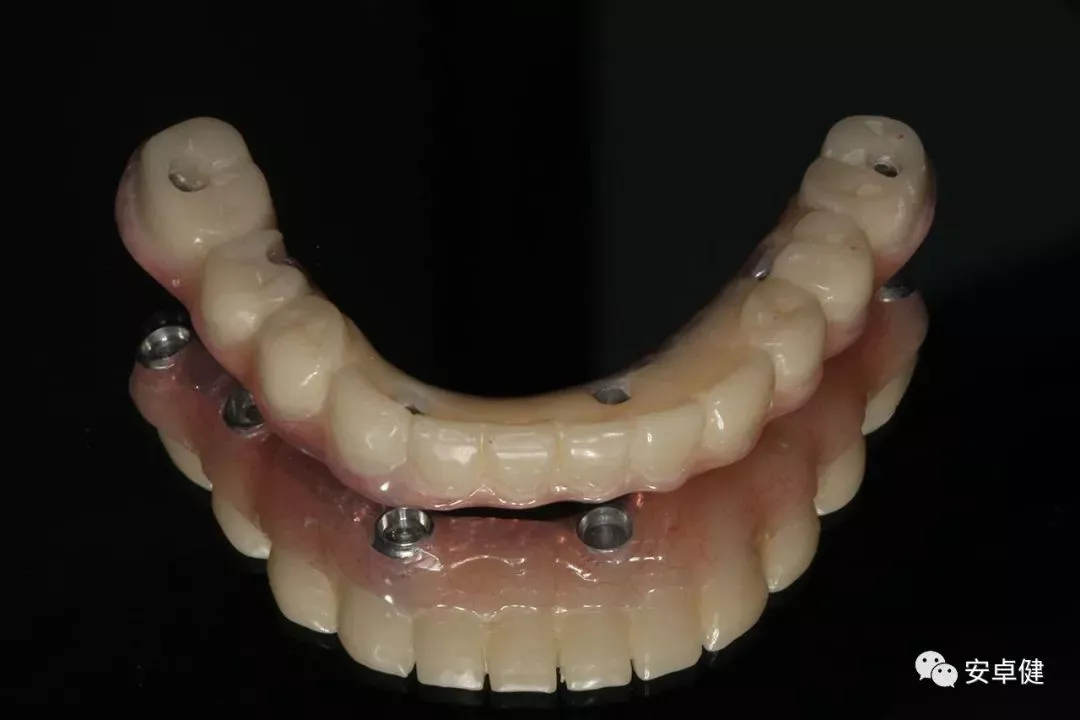

最终修复体合面照

最终修复体正面照

最终修复体正面咬合照

最终修复体侧面咬合照

▷ 永久修复

患者术后16个月:

• 于口内试戴原厂纯钛切削一体式桥架,并检查前牙排蜡外形及后牙咬合关系;

• 聚合瓷烤塑制作最终修复体;

• 为减少牙面磨耗,于后牙区制作360度防裂纯钛金属带;

• 试戴满意后,二级螺丝加力至15N;

• 特氟龙封闭螺丝孔,光固化复合树脂封闭上方螺丝通道,完成最终固定式种植义齿修复;